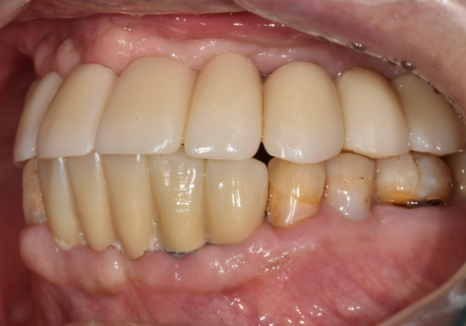

70대 당뇨 환자분의

상악 무치악 치료는 총 8개월이 걸렸습니다.

현재 환자분은 6개의 임플란트로

편안하게 식사를 하고 계십니다.

250308 (전) 251020 (후)